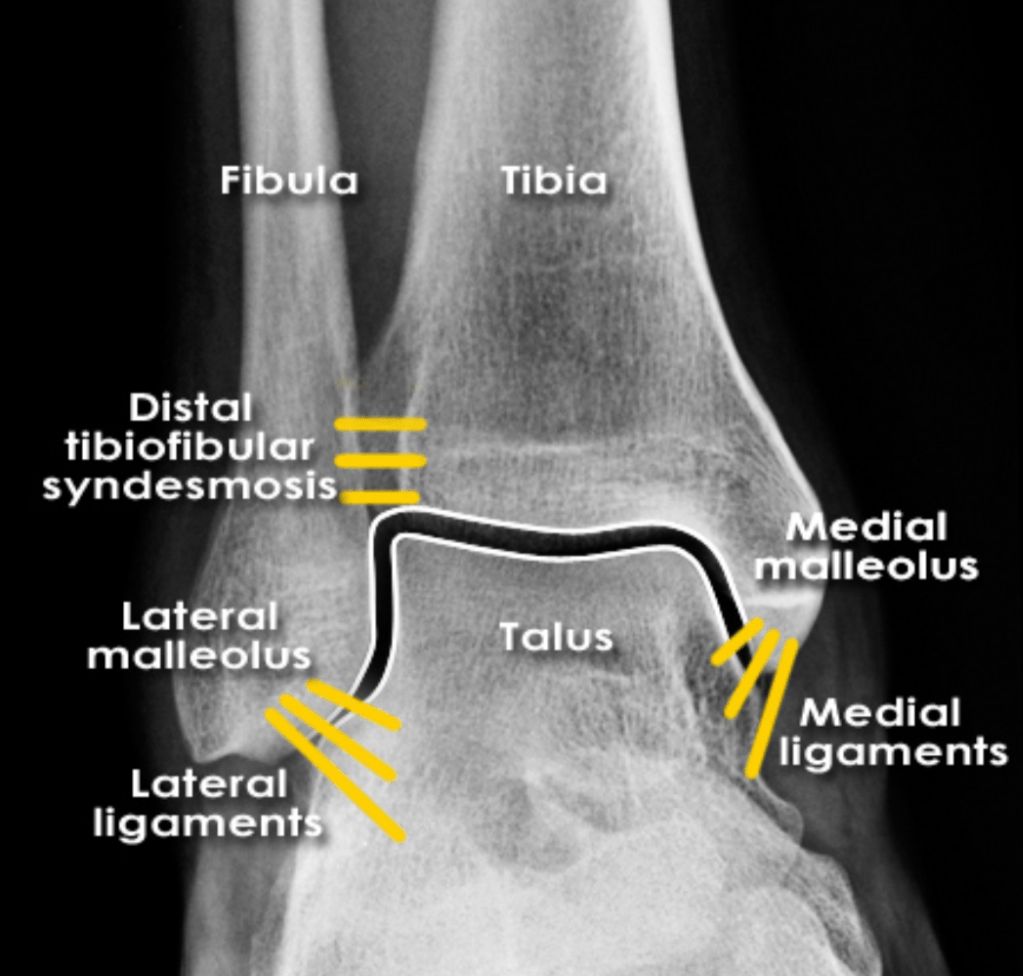

Name any abnormalities in the below imaging of ankle mortise

What is Normal?

What should you suspect if you see this image?

What is Maisonneuve Fracture?

Fracture of the proximal fibula associated with injury to the medial side of the ankle and disruption of the distal tibiofibular syndesmosis.

The medial ankle injury may be either a visible medial malleolus fracture or an invisible injury of the medial ligaments.